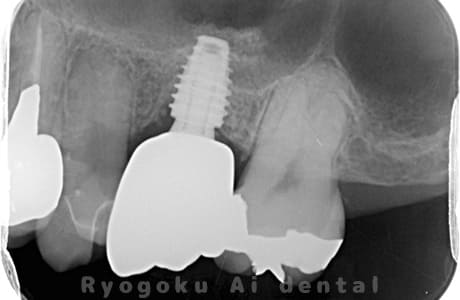

Case12

- 左下7番歯牙破折

-

- 治療内容

- インプラント治療

- 治療費用

- 約600,000円

左下の奥歯が痛いとのことでご来院された患者様です。歯が完全に割れており、保存が不可能であったため、抜歯を行い、その際に骨に変わるお薬を入れ、十分な治癒を待ってからインプラント治療を行いました。経過良好で、大変満足されました。

<リスク・副作用>

治療後、痛みや違和感、出血、腫れなどが出る事があります。喫煙者、糖尿病などの方の場合、歯が生着しない場合があります。